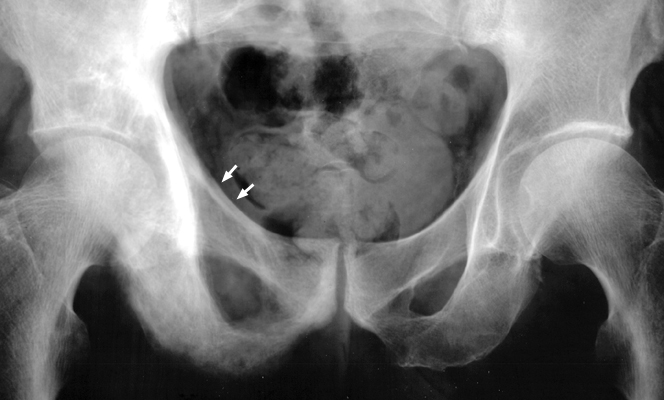

AP radiographs of the pelvis with changes characteristic of Paget's disease throughout the right hemipelvis. Notice the thickening of the right pelvic brim (ileopectineal line) as compared to the left. Thickening of the pelvic brim, or arcuate line (ileopectineal line) seen in patients with Paget's disease. The ridge of bone around the pelvic brim, when osteoblastic reaction occurs, adds to the normal sclerotic density of this area. This is a useful sign in distinguishing Paget's changes from metastatic disease.

AP pelvis - Click on the image for a larger versionAAP pelvis - Click on the image for a larger versionB